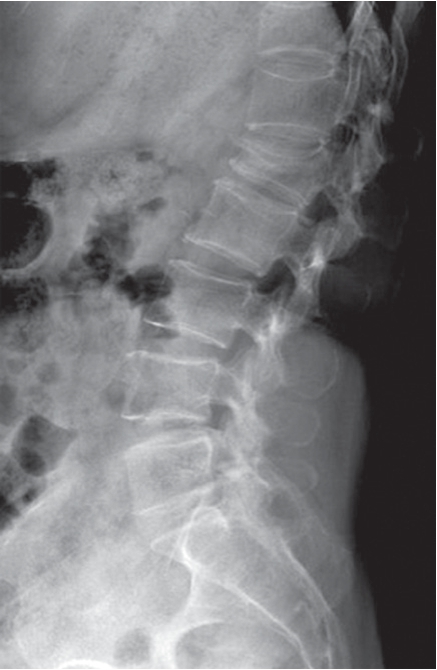

1.X线平片 X线平片表现为椎体前缘变短,侧位片椎体呈楔形,无骨折线,其上下椎间隙通常保持正常(图7-2-12)。

图7-2-12 X线侧位片显示压缩性骨折